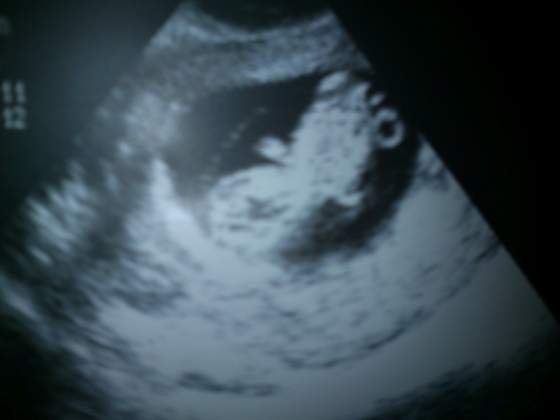

A to juz nasz bardziej czlekoksztaltny czlonek rodziny: DSC_0076.jpg w 10tc

Ania - WOW - widzę ogonek u tego małego człowieczka!!! śliczny :-D naprawdę go widzę :tak: ciekawe czy tak samo się ułoży w czwartek, bo jak tak, to może zamiast ogonka będzie widać "inny ogonek" albo brak ogonka.... he he he - już ma małe łapeczki. Nie no! naprawdę pięknie Ci się ułożył.

Tak, slicznie zaprezentowala sie kuleczka do zdjecia!! MOZe teraz we czw tez tak ladnie sie pokaze.Ale nie nastawiam sei,ze poznamy plec,mysle,ze lekarz jeszzce nie bedzie chcial ryzykowac nam takiej info na tym etapie.